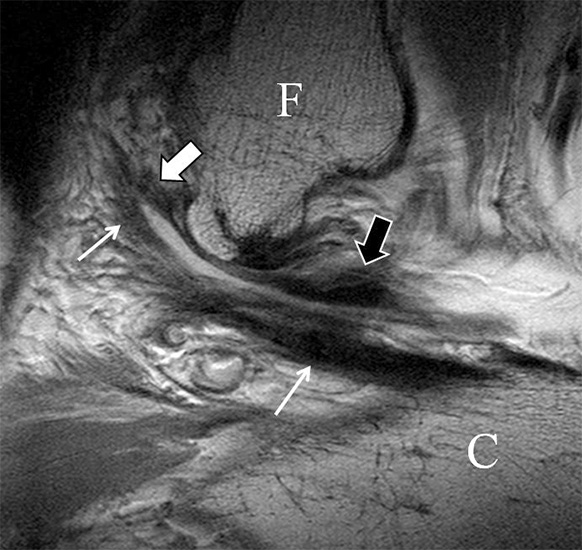

Das Ligamentum fibulotalare anterius entspricht einer bifaszikulären Struktur (Abb. 2 a) mit interponierendem fibrovaskulärem Gewebe (S. K. Sarrafian (ed). 2003). Es gibt jedoch Variationen der Ligamentanatomie. In 55% liegt das LFTA als bifaszikuläres Band (Abb. 2 a), in 9% als monofaszikuläre Bandstruktur (Abb. 2 b) und in 36% als multifaszikuläre, striäre Variante (Abb. 2 c) vor 3.

Das LFTA verbindet die antero-inferiore Fibulaspitze mit dem Processus lateralis tali und inseriert hier an einem oder zwei kleinen Tuberkeln 3. Der in Neutralposition horizontale Verlauf erleichtert die kernspintomographische Darstellung in dieser Standardebene. Das LFTA weist durchschnittlich eine Breite von knapp über 2 mm auf 4. Somit sind bei einer Routinedarstellung in 3 mm Schichtdicke Anschnittsphänomene, die die Diagnostik erschweren, regelmäßig anzutreffen. Dementsprechend sind auch die ligamentären Subfaszikel nicht zu differenzieren. In koronarer Darstellung ist dies aufgrund der hohen Auflösung in der Schichtebene jedoch möglich (Abb. 2 a-c), wobei hier wiederum eine Integritätsbeurteilung des Bandes erschwert ist. Unter Verwendung hochauflösender Techniken im Millimeterbereich (Schichtdicke) sind hingegen auch in der axialen Ebene die subfaszikulären Strukturen zu beurteilen (Abb. 3).